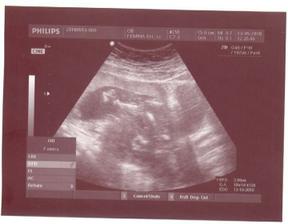

1.7.2010 - dalšia poradňa, tešíme sa....taaakže poradňa za nami, malý má už 813 g a pekne si oddychuje v brušku, ešte je stále nožičkami dole, ale hádam sa rýchlo otočí, dr. nám ešte povedala, že máme dosť nízko placentu, ale že ona sa ešte zdvihne vyššie, dúfajme.....